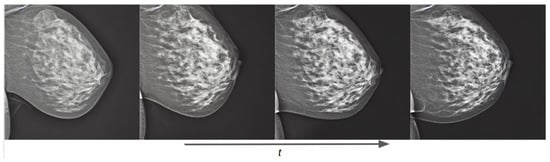

3.1.2. Joint OMI-H and VinDr Model: Concept Extrapolation

Besides allowing us to select the vendor type of the generated mammogram, the combination of both datasets permitted us to extrapolate the characteristics of one dataset into the other. This means that, e.g., the breast density of the generated Hologic mammograms can be controlled, even though this information was not available in the Hologic dataset. Figure 15 shows how the generated mammogram matches the text prompt characteristics as the training process advances, reducing the area and increasing the breast density.

Figure 15.

Training evolution of the diffusion process on a conditional pretrained model trained with both Siemens and Hologic images at epochs 1, 3, 7, and 40. The prompt is: “a siemens mammogram in MLO view with high density and small area”.